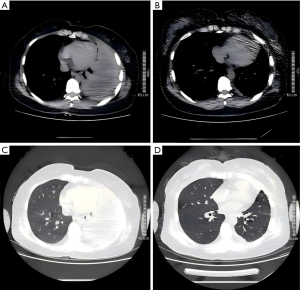

A total of 315 subjects were enrolled, including 54 in group A and 261 in group B. After 1:1 PSM, 49 subjects remained in each group. Missing data accounted for <5% of total data points across all baseline variables. Specifically, missing values were observed for the following variable: intraoperative blood loss (n=3) in the pre-matching cohort; no missing data were present in the post-matching cohort. All missing data were handled using single imputation to maintain dataset integrity. Before matching, baseline data showed imbalance between the groups, with significant differences in incision length (P=0.002), operation time (P=0.01), and intraoperative blood loss (P=0.04). Post-matching, no significant differences were observed in baseline characteristics, including BMI (P=0.93), gender (P=0.63), age (P=0.21), smoking history (P>0.99), hypertension (P=0.56), diabetes (P=0.48), coronary heart disease (P>0.99), concurrent pulmonary tuberculosis (P=0.41), use of H-R-Z-E anti-tuberculosis regimen (P=0.83), lesion site (P>0.99), intercostal location of incision (P=0.98), incision length (P=0.42), operation time (P=0.65), intraoperative blood loss (P=0.10), and number of thoracic drainage tubes (P=0.32) (Table 1). During the follow-up period, there were no cases of reoperation, death, empyema recurrence, or tuberculosis dissemination. Preoperative and postoperative CT imaging of representative patients (Figure 3) showed typical features of stage III tuberculous empyema, including compressed lung tissue, pleural thickening, and narrowed intercostal spaces preoperatively, with complete thoracic cavity expansion and near-normal intercostal spaces observed 3 months postoperatively.